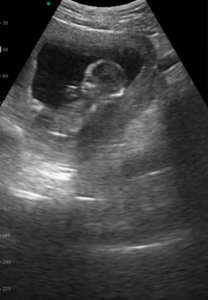

妊娠13週で見えた小さな命の躍動

投稿に映っていたエコーは、妊娠4ヶ月、13週のときのものです。

この映像は、医療機関での健診時ではなく自宅用のレンタル機器を使って撮影したものでした。

赤ちゃんはちょうど起きているタイミングだったのか、お腹の中で元気に跳ねたり回ったりと活発です。

その中でも特に目を引いたのが、まるでこちらに向かって手を振っているように見える瞬間でした。